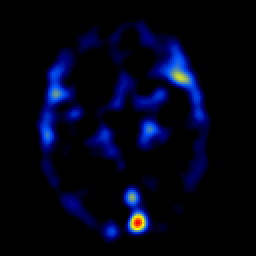

overlay -- Slice #11

[Home][Help][Clinical] Slice 11

Click on sagittal image to select slice. Click on thin tickmark to change timepoint, or thick tickmark for overlay.